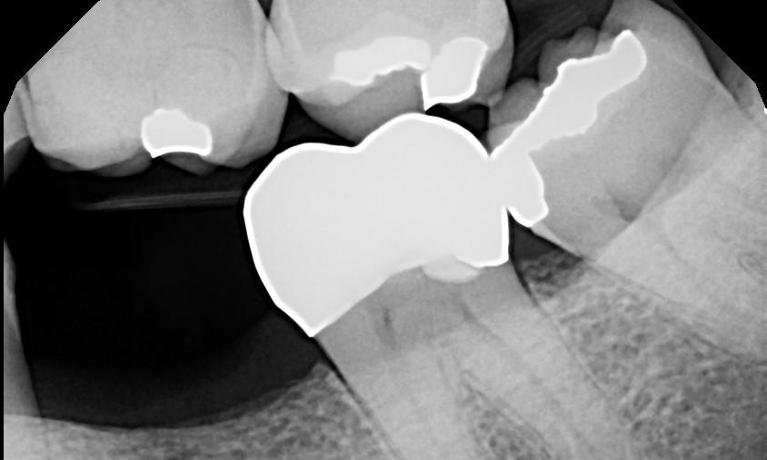

The tooth in the Before photo has a silver filling with quite a few cracks in the tooth. All back teeth have peaks (cusps) and valleys (grooves) allowing to chew your food. Cracks often occur in the valleys of these teeth and around the peaks. These cracks increase the potential for these peaks to break off over time. On this tooth we monitored the cracks and when they began increasing in size, we recommended a crown. A crown (sometimes referred to as a cap) surrounds the tooth 360 degrees. This prevents any part of the tooth or the peaks ...